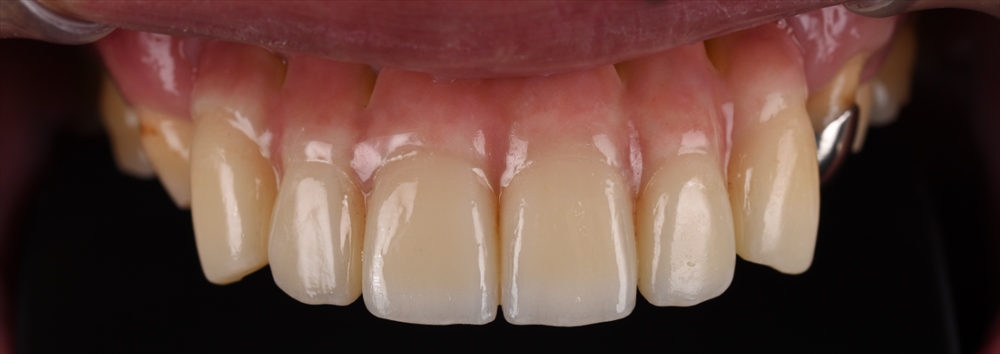

残念ながら上の前歯は保存が出来ませんでしたが他は歯周基本治療(MINST)を私が行い

治しました。

歯周外科は行わず基本治療(歯茎を切らずマイクロスコープのみ)で

すべて3mm以内のポケットになっています。

仮歯のコントロールをまた半年行い

本日

元々重度の歯周病とは誰も思わない歯肉です。

治療終了です。